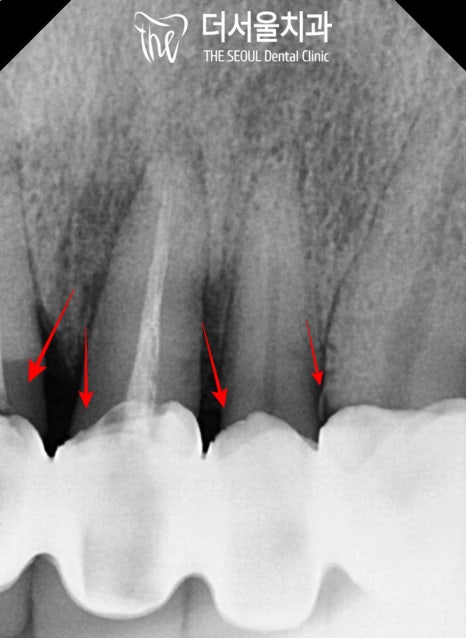

그중에서 주된 불편감을 호소하시는 앞니는

기존 보철 하방으로

이차 충치가 생겨있는데요,

충치로 인해 건전 치질이 약해져있다 보니

작은 힘에도 아슬아슬하게 흔들리며

부러지기 일보 직전이었습니다.

앞서 보여드린 것처럼

파노라마, 치근단, 3차원 CT 촬영을 통해

수술에 적합한 구강인지 판단합니다.